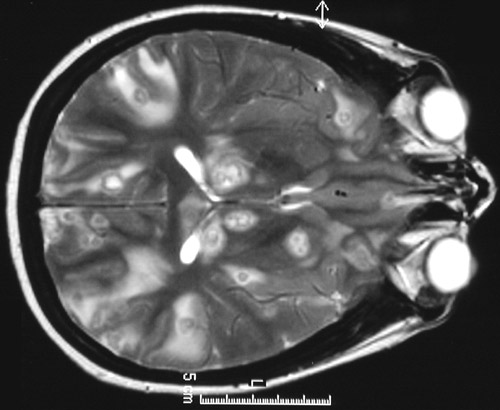

The T2 weighted MRI scan above and the FLAIR scan below demonstrate numerous brightly enhancing

ring enhancing abscesses

with prominent surrounding

edema

, which is bright on these scans. These are

Nocardia braziliensis

abscesses.